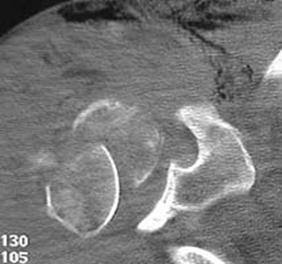

Fractura de acetabul Fractura de acetabul. Aspect CT